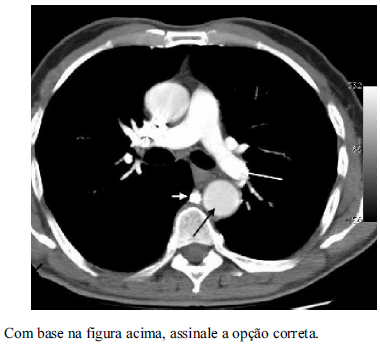

A tomografia computadorizada do tórax é largamente empregada na propedêutica de avaliação de diversas doenças mediastinais e pulmonares. A respeitos dos aspectos técnicos relacionados a esse tema, assinale a opção correta.